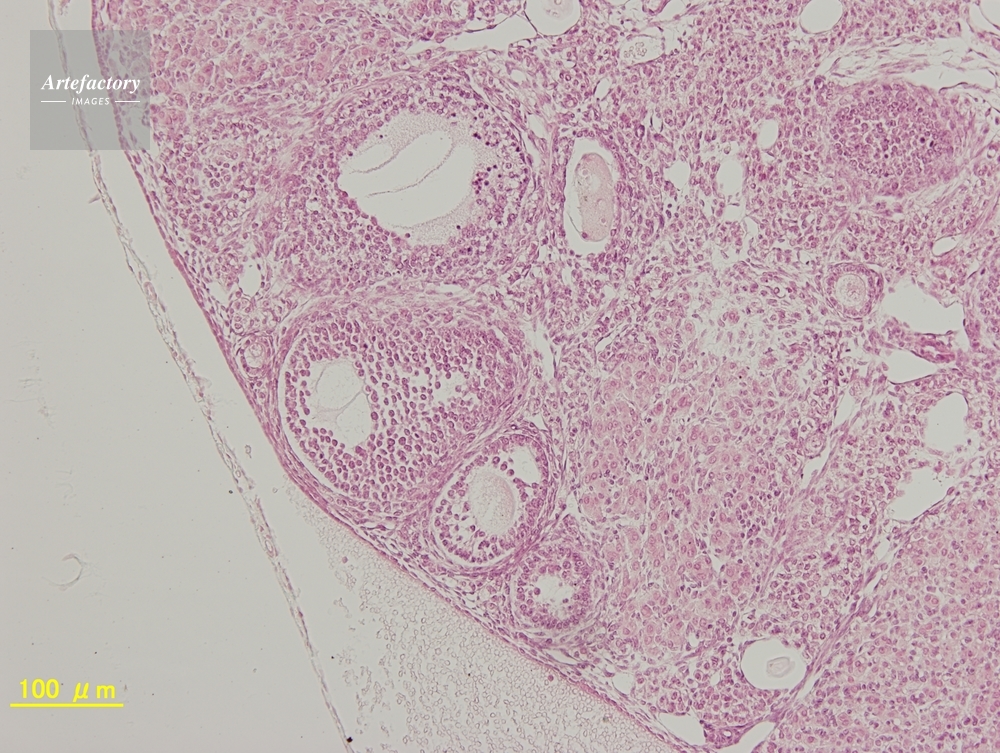

| 作品タイトル | マウス,卵巣 | モデルリリース | なし | |

| 作家 | OLYMPUS CORPORATION Technolab | プロパティリリース | なし | |